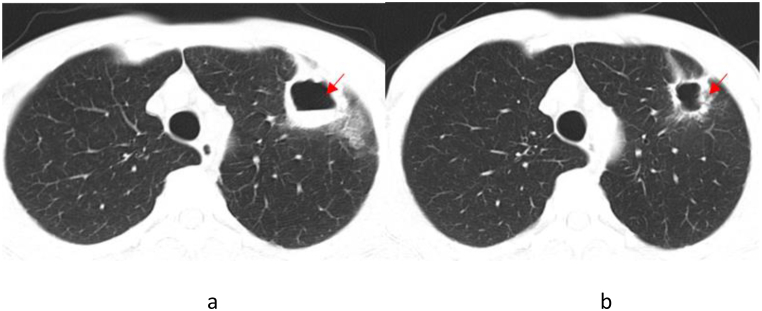

Patient 2, upon admission, was initially treated empirically with a combined medication of piperacillin-tazobactam and moxifloxacin. Despite the confirmed diagnosis of pneumonia caused by TW infection based on expert group’s discussion, re-examination of chest CT demonstrated improved condition in lung lesions (Fig. 2(a and b)). But the patient declined to accept the standard treatment for WD, and was discharged. At present, the patient still has occasional cough and expectoration.

Fig. 2.

Chest CT Scan of Patient 2 (The dates from left to right are August 22, 2022 (a) and September 2, 2022 (b)). The arrowhead shows the focus.